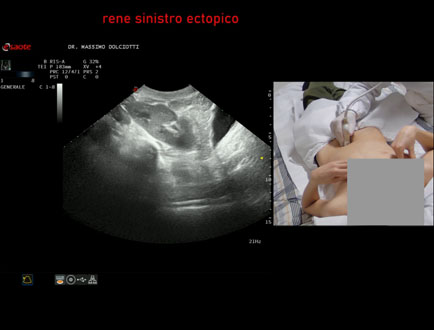

Motivazione dell'esame: riscontro occasionale di ectopia renale sinistra

Commento all'esame: le immagini ed il video documentano il rene sinistro ectopico in sede pelvica, di ecostruttura regolare e morfovolumetria normale, con diametro bipolare di 99 mm (v.n. 90-120 mm) x 37 mm, non dilatazione della via escretrice sinistra.

Conclusioni: rene sinistro ectopico (ectopic left kidney).